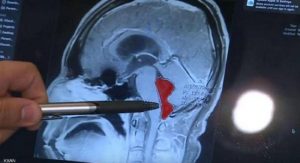

دودة في دماغ رجل لمدة 10 سنوات .

سماح عقيق/ صوت العدالة. في حالة طبية ناذرة، كشفت الفحوصات عن وجود دودة شريطية، داخل دماغ رجل، والأدهى انها استقرت في موقعها لنحو 10 سنوات. كان جيراردو الذي يعيش في [...]